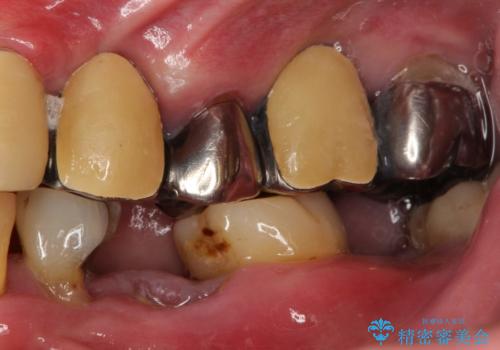

虫歯だらけ、歯周病 崩壊した口腔の再建 フルマウスリコンストラクション

- 歯周外科・インプラント・顕微鏡下根管治療などを含んだ総合的な治療を計画した。

かみ合わせの力が非常に強く、夜間の歯ぎしり・食いしばりもひどかったため、奥歯はメタルオクルーザルの設計でかぶせ物を製作しています。